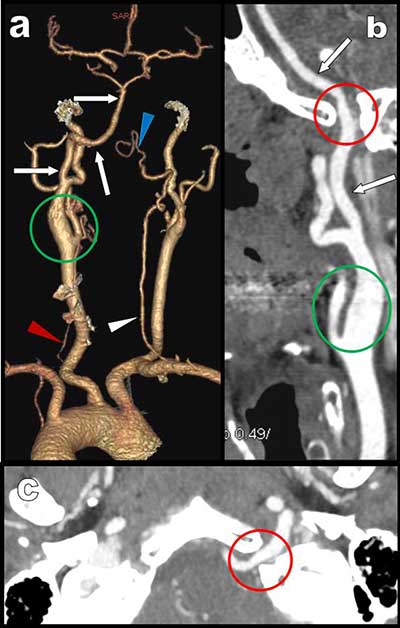

Figure 1

CTA: a) posterior-anterior VR view show major hypoplasia of the vertebral arteries. They are not connected to the basilar trunk which appear only feed by a large ascending artery emerging from a large left internal carotid. Curvilinear reconstruction (b) and axial MIP view (c) at the level of the foramen magna show this large hypoglossal artery penetrating the skull through the supracondylar hypoglossus canal.